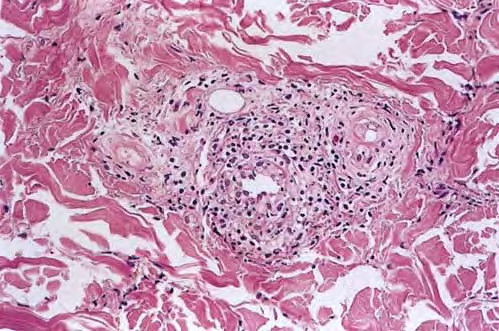

Pernio = الشرث Pernio (Chilblain) Pernio (chilblain) is a distinct form of cold-induced injury in which humidity, in addition to cold, plays a role in inducing the condition . There are acute and chronic presentations. Chilblains classically presents in young to middle-aged women as painful, burning, and/or pruritic erythematous to violaceous or cyanotic macules, papules, […]